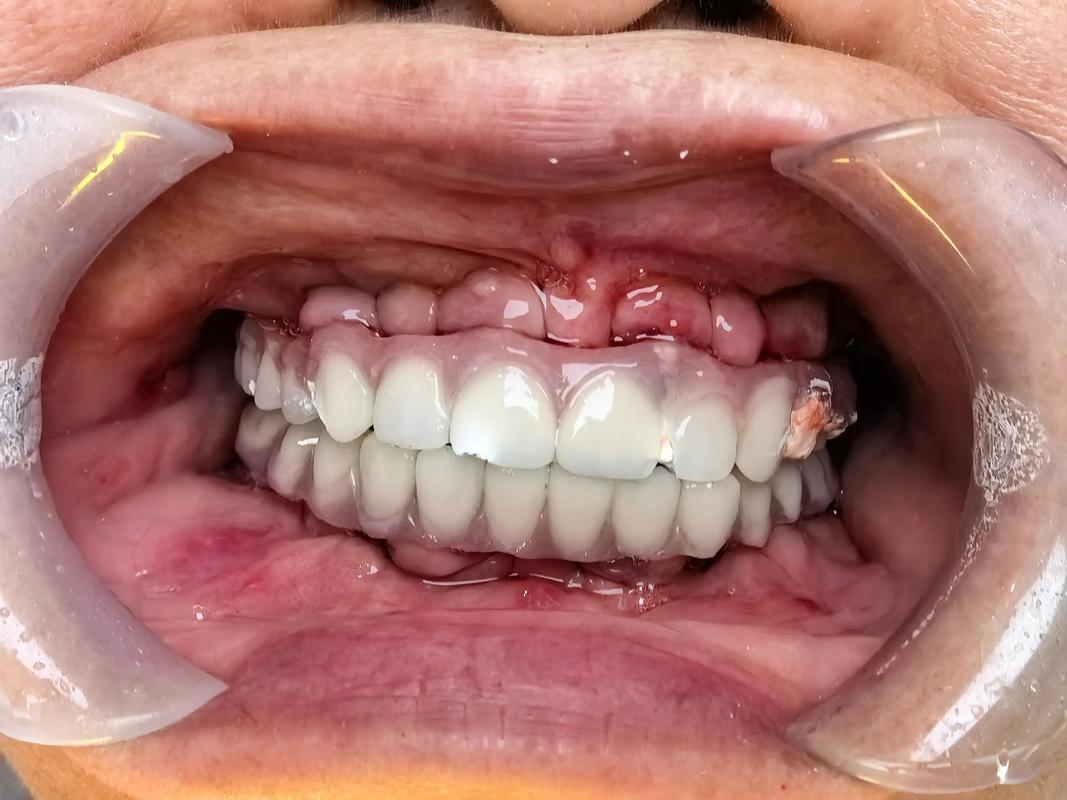

(图片来源网络,侵删)